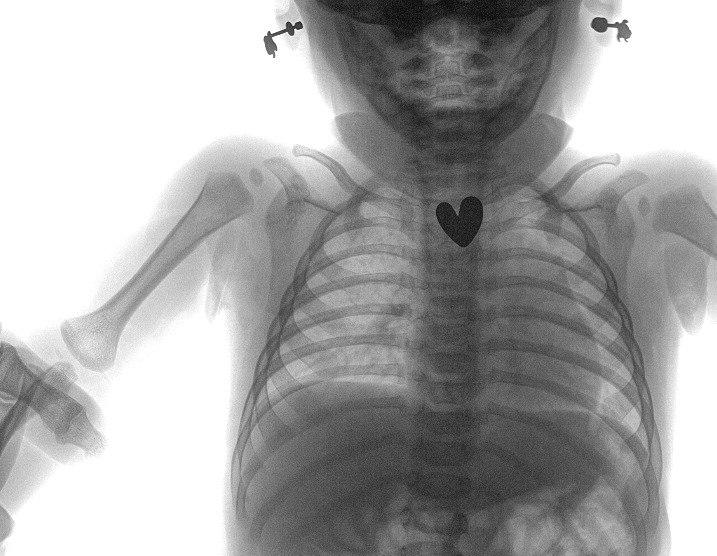

Ему сделали рентген-снимок и в верхней области пищевода обнаружили инородное тело — серёжка в форме сердца размером 1,5 см. Ребенка госпитализировали в хирургическое отделение, провели исследование пищевода, желудка и начального отдела кишечника.

Поскольку серёжка-гвоздик имела острый наконечник и сердцевидную форму, ее спустили в желудок, чтобы избежать травм.